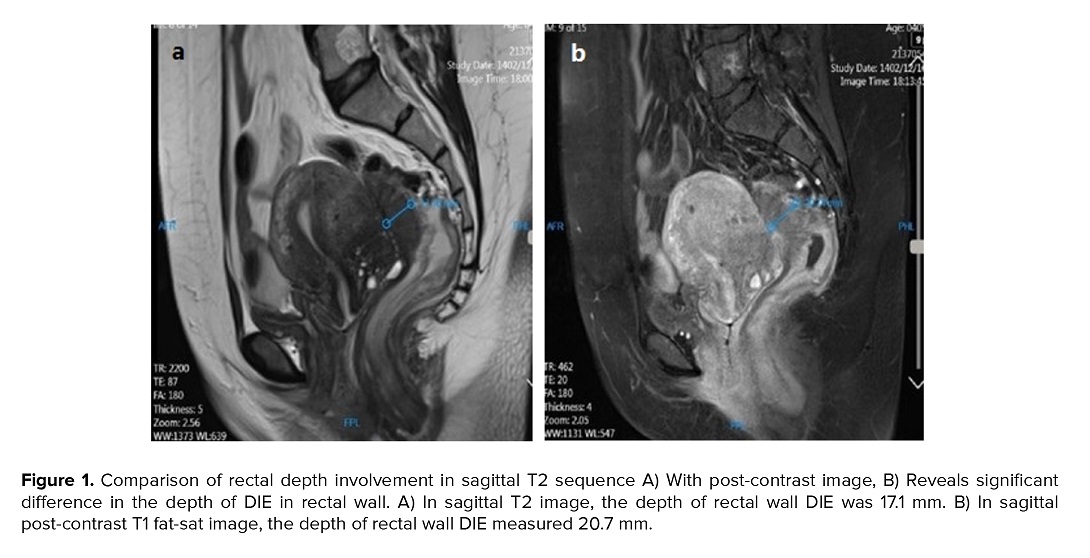

Conversely, for rectosigmoid and posterior uterine wall endometriosis, contrast-enhanced MRI highlighted greater lesion depth and posterior wall thickness (Figure 1a, b), findings aligned with a 2019 Chinese study (14). However, the number of detected lesions in the uterosacral ligaments and torus uterinus decreased significantly on post-contrast images, reinforcing the superiority of non-contrast imaging for these sites (7).

Table III provides a detailed evaluation of the depth of DIE, comparing findings between pre- and post-contrast MRI images. Regarding the depth of DIE, contrast-enhanced imaging significantly increased the detection of rectal wall involvement (p = 0.026) and posterior uterine wall involvement (p = 0.04) (Table III).